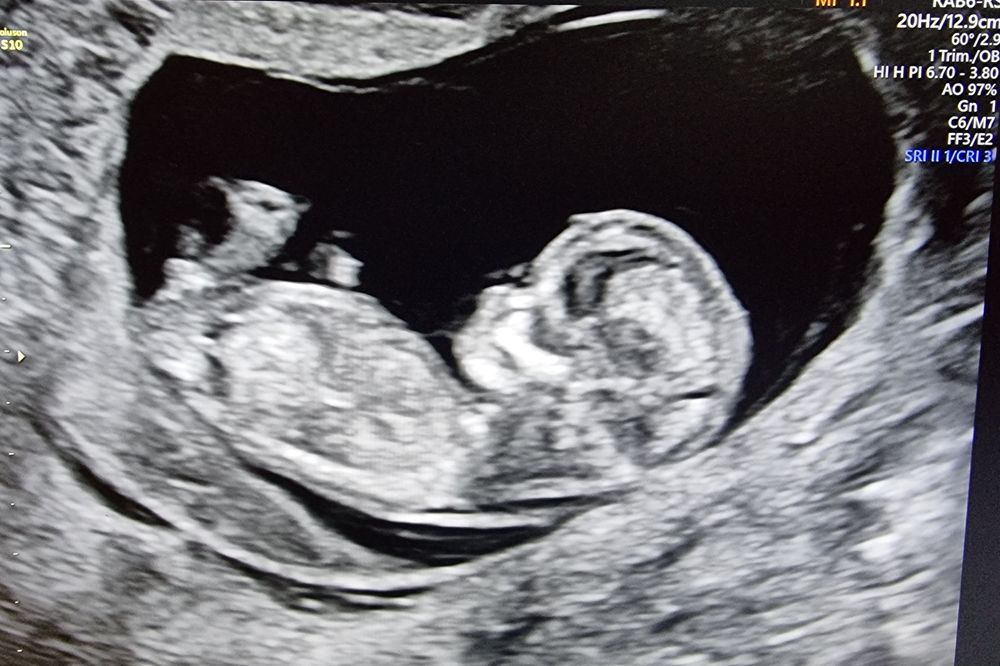

Вот все пишут мальчик, а я смотрю, так бугорок почти параллельно, как у девочек.. Или я не туда смотрю? 😅

Nina, да мне тоже кажется, что вниз смотрит, а не торчком вверх)) но этож так пока, забавы ради) потом напишу кто получится))

Это сагиттальный срез, по нему нельзя рассмотреть пол ), зато хорошо виден сам эмбрион

То что я вижу, торчит прям вверх) у меня с таким фото мальчик)

У меня с сыном бугорок вверх торчал.